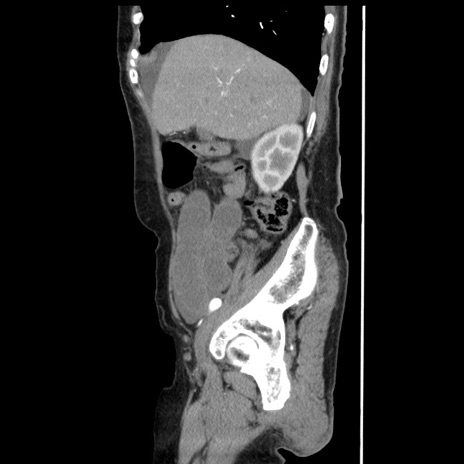

症例1(矢状断像)

【症例】80歳代女性

【主訴】腹痛

【現病歴】8時間前から腹痛あり来院。

【既往歴】糖尿病、脂質異常症、子宮体癌にて子宮全摘術

【身体所見】意識清明・会話良好だが腹痛で苦悶様、全腹部にわたって反跳痛と圧痛あり

【データ】WBC 13600、CRP 0.14、LDH 224、CK 90